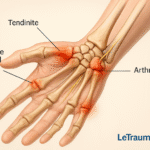

La tendinite du poignet désigne l’inflammation ou l’irritation des tendons du poignet. Les tendons sont des tissus fibreux qui relient les muscles aux os, permettant ainsi le mouvement. Cependant, lorsqu’ils sont surutilisés ou blessés, ces tendons peuvent s’enflammer, entraînant des douleurs et limitant les mouvements.

Les tendons les plus souvent touchés par la tendinite du poignet sont les tendons fléchisseurs et extenseurs. De plus, ces tendons contrôlent les mouvements des mains et des doigts, essentiels pour des tâches quotidiennes telles que taper au clavier, écrire ou saisir des objets.

La tendinite du poignet est souvent confondue avec le syndrome du canal carpien. Toutefois, ces deux affections sont distinctes. Le syndrome du canal carpien implique une compression du nerf médian au niveau du poignet, provoquant des engourdissements et des picotements. En revanche, la tendinite concerne principalement l’inflammation des tendons, entraînant des douleurs et un gonflement.